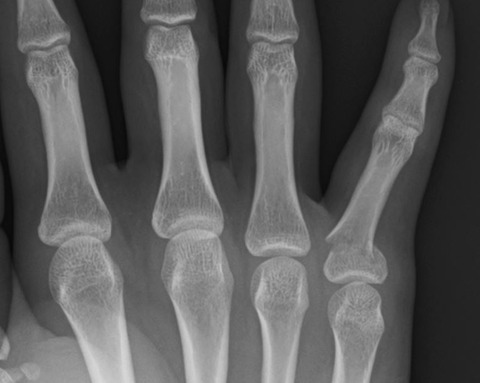

先日、小指の基節骨基部骨折の手術がありました。

この部位の骨折は尺背側に転位する傾向にあり、中・高生に多い印象を抱いています。

中・高生なのでできるだけ保存治療をしたいという思いがあり、昔はがんばって徒手整復を試みましたが、やはり満足のいく整復位を得ることはできないことが多いです。

このため最近では、牽引して整復位を獲得できないことが分かれば、あっさり手術をする方針に転換しています。今回の症例も牽引だけでは徒手整復できませんでした。